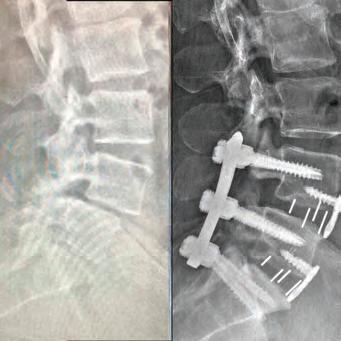

Led by Dr. Courtney, the skilled team at Advanced Spine Center cares for patients with neck and back pain using a wide array of the most state-of-the-art tools and techniques—from conservative physical therapy and injection therapy—to advanced pain manage-

BOARD-CERTIFIED,

ORTHOPEDIC SPINE SURGEON PRACTICING FOR 27 YEARS.

ment, as well as surgical intervention. We employ the latest in minimally invasive spine surgeries, in addition to cutting-edge replacement technology. Incorporating both high tech and high touch, we get our valued patients back to their lives so they can enjoy all the activities they love.

SURGERY: L5/S1 360° LUMBAR FUSION

Lori Juarez

SURGERY: L4/5, L5/S1 360° LUMBAR FUSION